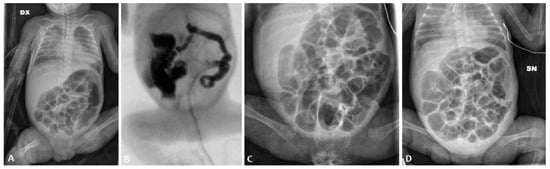

At admission (weight 650 g), an abdominal X-ray (AXR) confirmed the presence of a diffuse dilated bowel with no evidence of intra-abdominal free air (Figure 1A), and an abdominal ultrasound revealed no signs of pneumatosis. Relevant abdominal distention persisted at AXR for the next 15 days despite enteral fasting; during this period, there was no spontaneous stool production. A contrast enema was performed on day 26 using the nonionic dimer contrast agent iodixanol 320 (Visipaque), and it showed a diffuse reduction in colon caliber with multiple fecal residues (Figure 1B).

Thus, the patient received a 15-day course of NAC by nasogastric tube (twice a day) and rectal enemas (once daily). This treatment protocol resulted in an increase in mean daily stool frequency and consistency. AXR findings before and after the NAC treatment course are shown in Figure 1C,D.

Figure 1. Abdominal X-ray of patient P1 on the 10th day of life (A); contrast enema performed on the 26th day of life (B); abdominal X-ray before the NAC treatment (C) and after the NAC treatment (D).